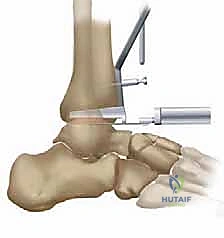

5. زراعة نظام TNK النهائي

بمجرد التأكد من المقاسات والزوايا المثالية، يتم زرع المكونات النهائية. يتم إدخال المكون الظنبوبي المعدني بقوة ليثبت في العظم، يليه المكون الكاحلي. أخيراً، يتم إدخال الح